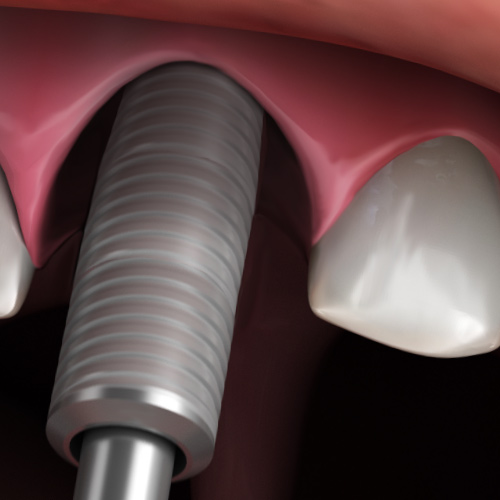

Implantology Updates

Monday, November 6, 2023

This Compendium eBook features a continuing education (CE) article on hard- and soft-tissue augmentation for implant therapy in the esthetic zone. This eBook also includes a case report article on a minimally invasive technique for the reconstruction of class III sockets with simultaneous i...